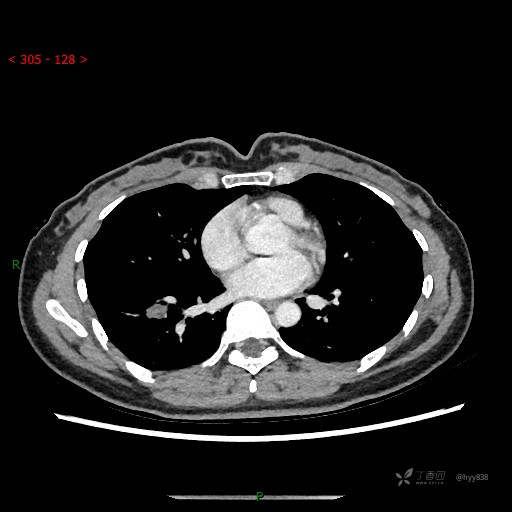

静脉期